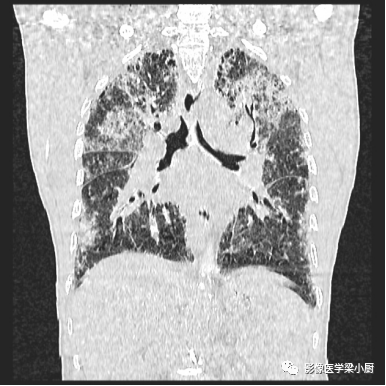

1.分布:90%的IPF患者HRCT表现为胸膜下分布。

分布的不均匀性:HRCT肺外周部位和胸膜下区不均匀分布,正常肺组织和病变区(网格、牵拉性支气管扩张或蜂窝)交替。病变常呈双侧不对称分布。

2.网格:网格影一般分布于两肺基底部、胸膜下,常伴结构扭曲。网格影不等同于小叶间隔增厚。

3.蜂窝:呈镞状囊性低密度影,囊壁光整,厚度1~3mm,直径常为3~10mm,偶尔可达2.5cm。蜂窝是HRCT的UIP型最具特征性的表现,蜂窝影预测UIP的灵敏度和特异度较高。

蜂窝的组成目前尚不清楚,推测为扩张的小气道,是纤维化进展的标志,提示预后差。

双肺呈弥漫蜂窝状改变

4.磨玻璃密度影:网格内磨玻璃密度影(ground-glass opacification,GGO)代表低于HRCT分辨率的肺纤维化病变,一般不超过网格范围。

而网格、蜂窝及牵拉性支气管扩张、细支气管扩张范围外的GGO则提示感染或其他疾病。

5.肺结构扭曲:影像学上将肺结构扭曲定义为肺小叶结构的改变(从多边形到变小的三角形)、非节段分布(跨越叶间裂胸膜);还可表现为胸膜表面和支气管血管束不规则。

6.尖-基底分布:UIP典型分布于基底部,但也可分布于上肺。当肺基底部以上肺区内出现网格影,同时伴肺下叶蜂窝影,可诊断UIP。